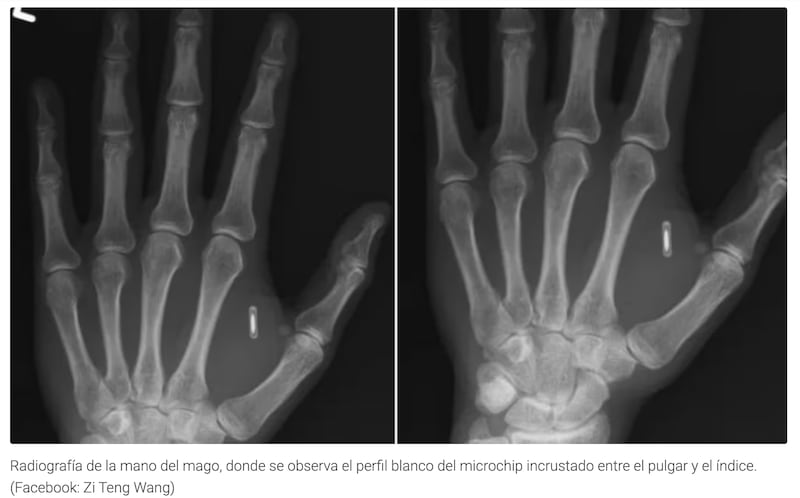

El chip implantado era un dispositivo NFC (Near Field Communication) o similar, capaz de almacenar datos e interactuar de forma inalámbrica con otros dispositivos (como teléfonos o sistemas de luces) mediante un toque o un gesto.

La implantación del chip, aunque un proceso invasivo y costoso, había sido exitosa y el hardware estaba perfectamente alojado bajo su piel, listo para ser programado.